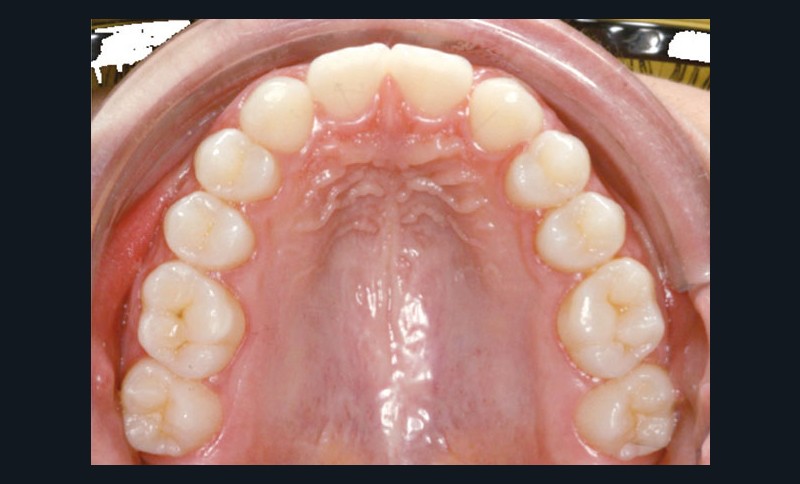

Cette jeune patiente de 6 ans se présente à la consultation avec une panoramique de dépistage révélant l’agénésie des deux incisives latérales permanentes (fig. 1).